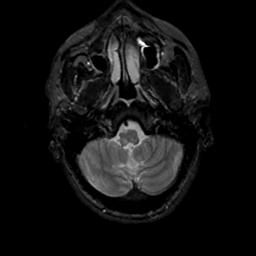

MR Study #17, July 7, 1991 -- Slice #7